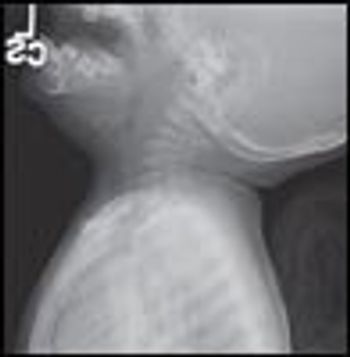

Ill-appearing 4-year-old girl with high-grade fever, without chills or rigors, and cough of 3 days’ duration. She also had a sore throat and was unable to move her neck because of pain. No history of rhinorrhea, difficulty in breathing, vomiting, or diarrhea. She had had tonsillitis 2 weeks earlier that was treated with a 1-week course of amoxicillin. Medical history otherwise unremarkable. Immunizations up-to-date.